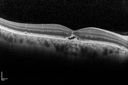

Best Disease - SD OCT Line Scan1244 views00000

(0 votes)